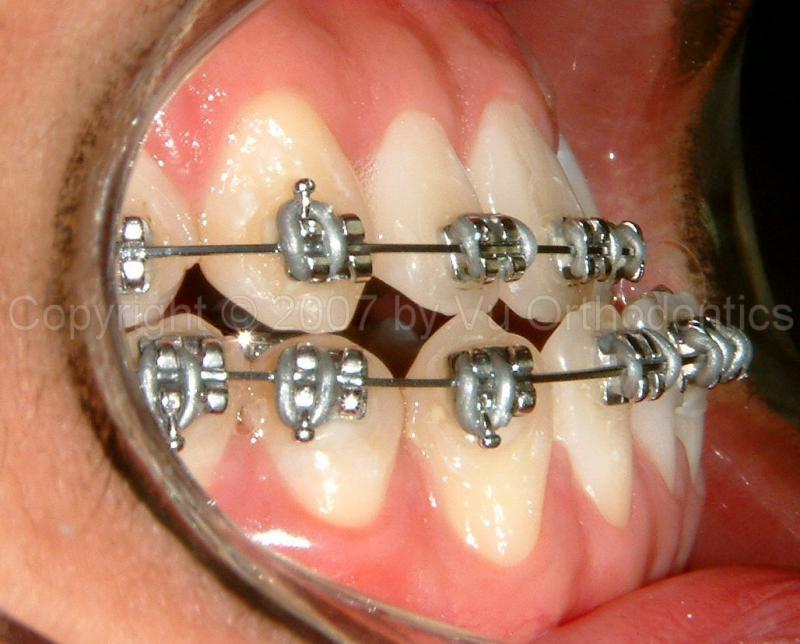

Case 5: 21 yr-old male

This case is skeletal Class III (moderate, with Class III malocclusion, with molars not shown); treated without orthognathic surgery and without extraction. Patient wanted no orthognathic surgery.

Fig. 11 View shows negative ovejet (initial): (a) Patient had braces elsewhere with treatment plan of orthognathic surgery, but he wanted no surgery; (b) After existing braces are removed.

Fig. 12 View shows progress (9 months): with Class III mechanics and no surgery